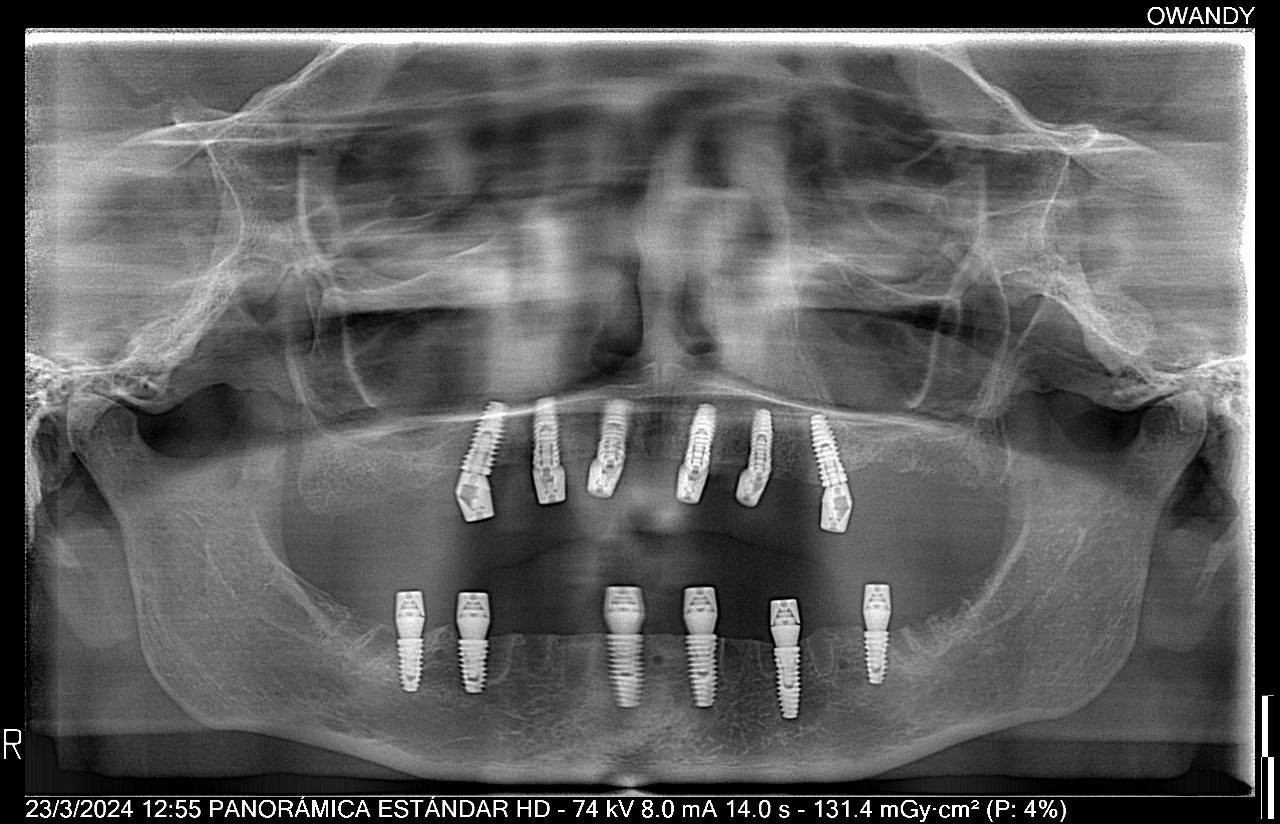

Implante Dental de Titanio y Circonia

La implantología dental se encarga de reemplazar piezas dentales perdidas mediante implantes de titanio que actúan como raíces artificiales. El Dr. José Abel Vargas, especialista en implantología, combina tecnología avanzada y técnicas de precisión para devolver la función masticatoria, la estética y la confianza en cada sonrisa, asegurando resultados duraderos y naturales.